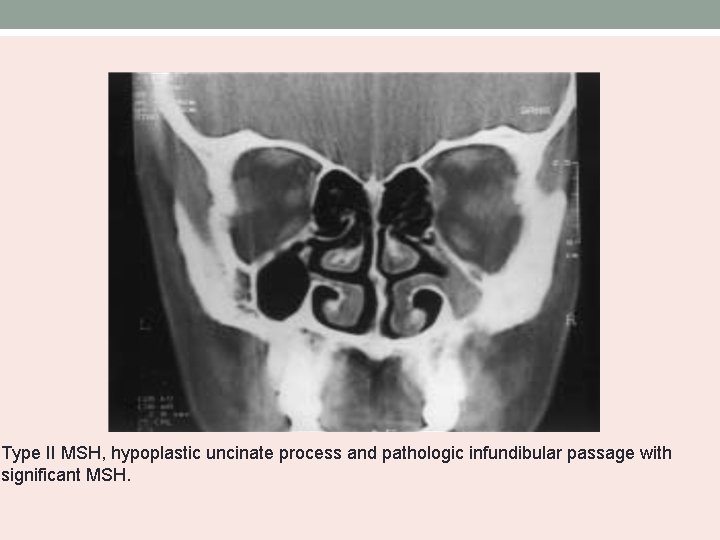

Bolger’s MSH Classification • Based on the degree of pneumatization and lateral nasal wall abnormalities. Type Uncinate process MSH I normal mild II Absent severe III Absent Cleft-like

Type II MSH, hypoplastic uncinate process and pathologic infundibular passage with significant MSH.